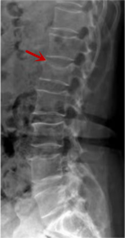

箭頭提示腰1椎骨折

箭頭提示腰3椎體滑脫